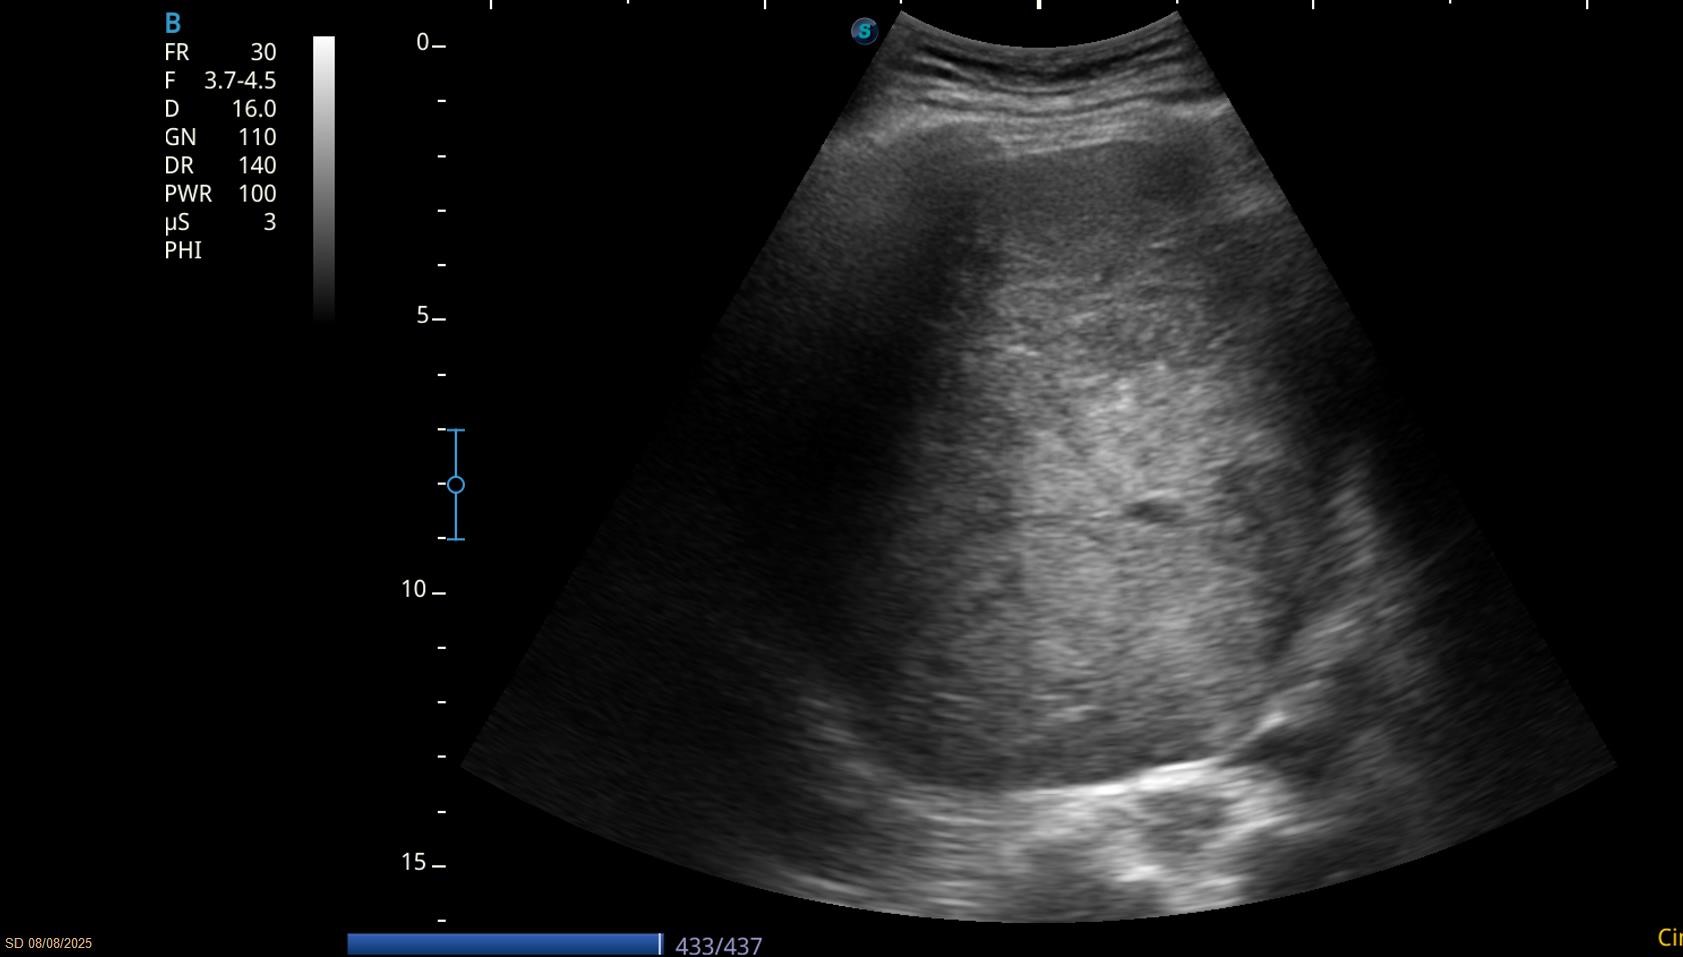

Debido a la alteración analítica se realiza una ecografía abdominal en la consulta.

Hallazgos ecográficos

Eco abdomen: Hígado de tamaño normal, nódulo en LHI de 2 cm y una gran masa heterogénea mal definida de unos 10 cm.

Resto dentro de la normalidad.